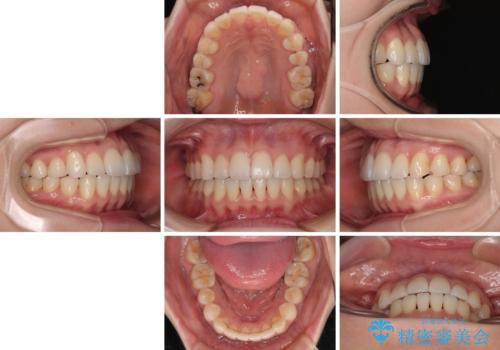

舌のトレーニングは不十分でしたが、1年半ほどで治療を終えることができました。

舌の突出癖が残っていると、容易に後戻りしてしまうため、トレーニングは継続するように指導しています。